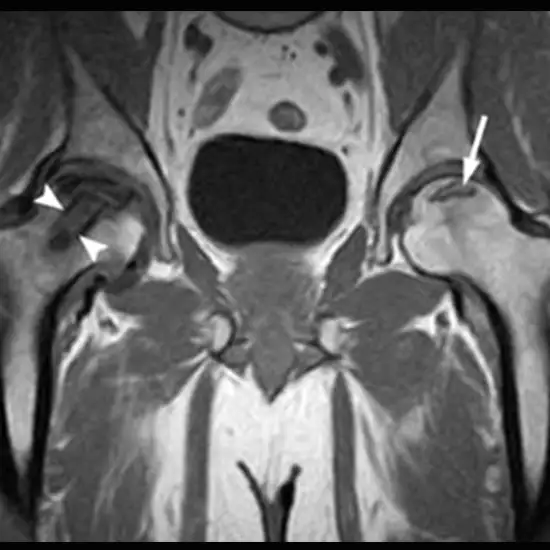

MRI(Magnetic Resonance Imaging) of the Hip joint with femoral is used to view the hip joint, hip bone, thigh bone, and the surrounding soft tissues like cartilage, tendon, ligaments, muscles, and blood vessels. This scan is used to diagnose the problems with the hip bone (The bone that forms the hip joint) as well as the thigh bone

Doctors prescribe this scan to evaluate the hip joint, hip bone, and femur(the bone of the thigh) and find the underlying problems.

• Fracture of the hip bones

• Hip dislocation and hip arthritis

• Fracture of the thigh bone

• Infections or inflammation of the hip joint as well as its surrounding soft tissues

• Presence of abnormal growths in the hip joint area